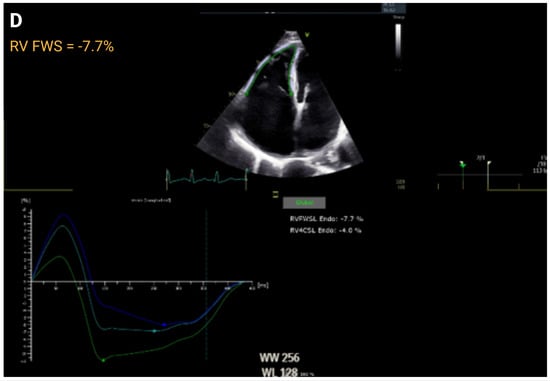

| RV FWS, % | >20 | ≤20 to <15 | <15 to ≥11 | <11 | r = 0.69 to 0.92 | |